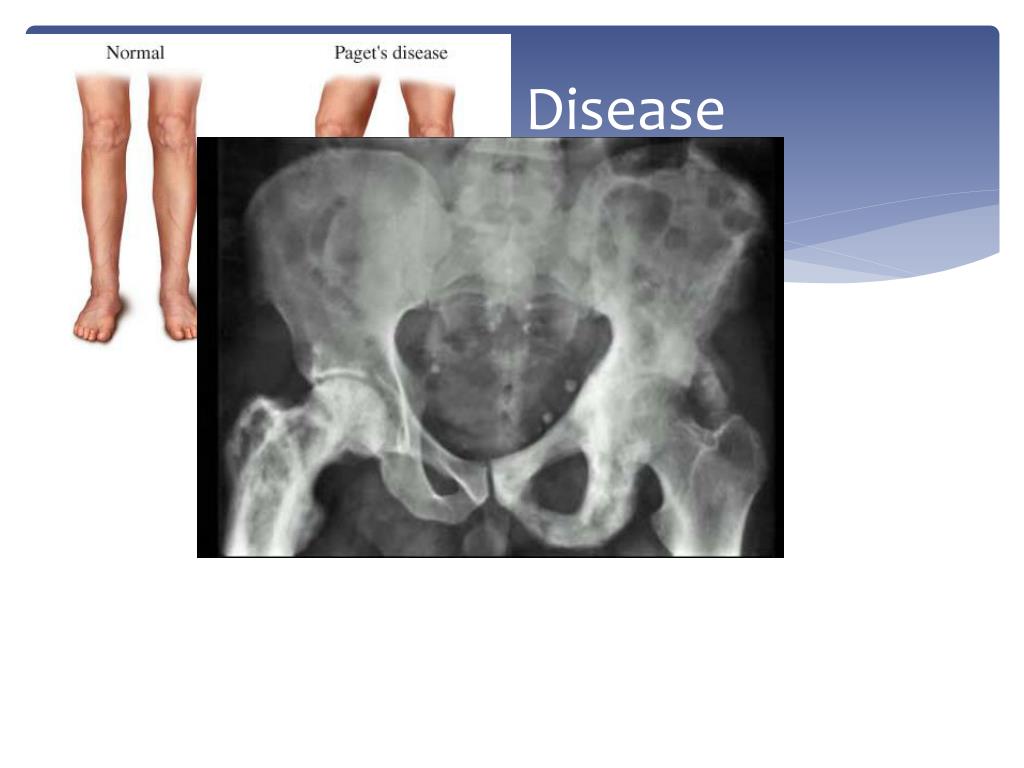

25. Pagents Disease